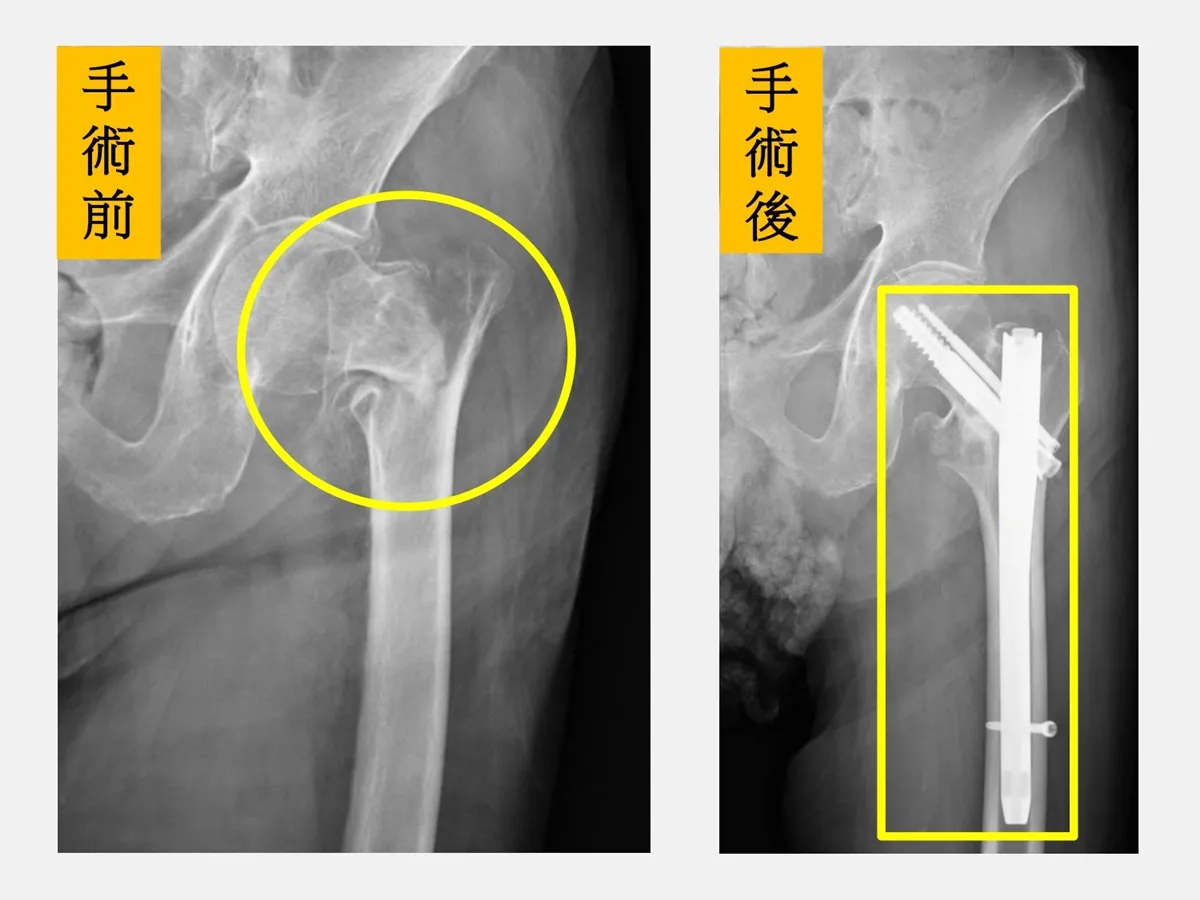

陳老先生痛到完全無法動彈,家屬急忙叫救護車將他送到仁愛長庚合作聯盟醫院急診,X光發現他左側髖關節粉碎性骨折。原本家人很擔心,因為聽說老人髖關節骨折後很容易致命或是引發殘障,後來在骨科部黃贊文部長的安排下順利完成骨折固定手術。

黃贊文部長指出,台灣已邁入超高齡社會,長輩跌倒骨折的案例屢見不鮮,其中「髖關節骨折」是最難處理的一種。髖部骨折後一年內的死亡率高達20%,主因是行動不便,不僅臥床照顧極為麻煩,更容易引發原有內科疾病的併發症,因此需要整個醫療團隊的整合照護。